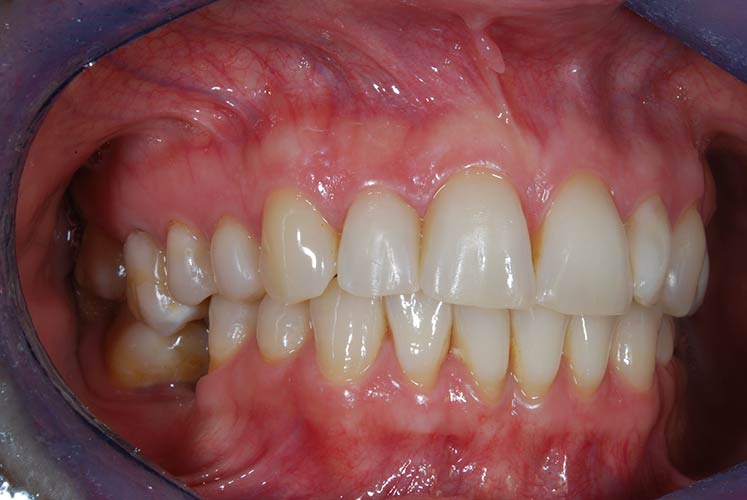

Con protesi fissa superiore e protesi fissa inferiore

I denti irrecuperabili dell'arcata superiore ed inferiore del paziente di anni 65

sono stati sostituiti da 10 impianti, cioè protesi radicolari endo-ossee che sostengono le protesi fisse superiore ed inferiore.